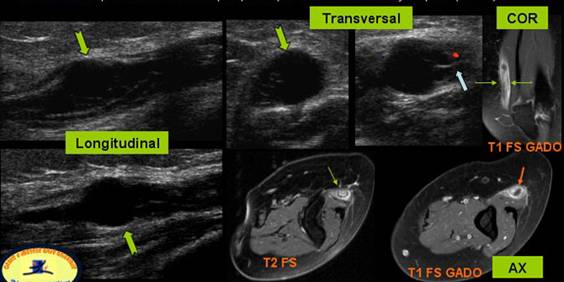

CHIST MUCOID INTRANEURAL AL NERVULUI ULNAR

Parestezii de lunga durata a degetelor 4 si 5

Structura chistica ce disociaza filetele nervoase → cu hiperemie in perinerv →

Pe IRM se evidentiaza hipertrofie nervoasa in T2 si prinde contrast in periferia chistului in T1